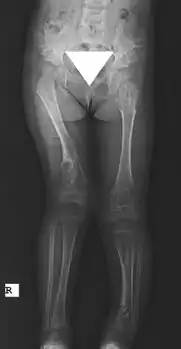

X-ray hips and legs: multiple enchondroma